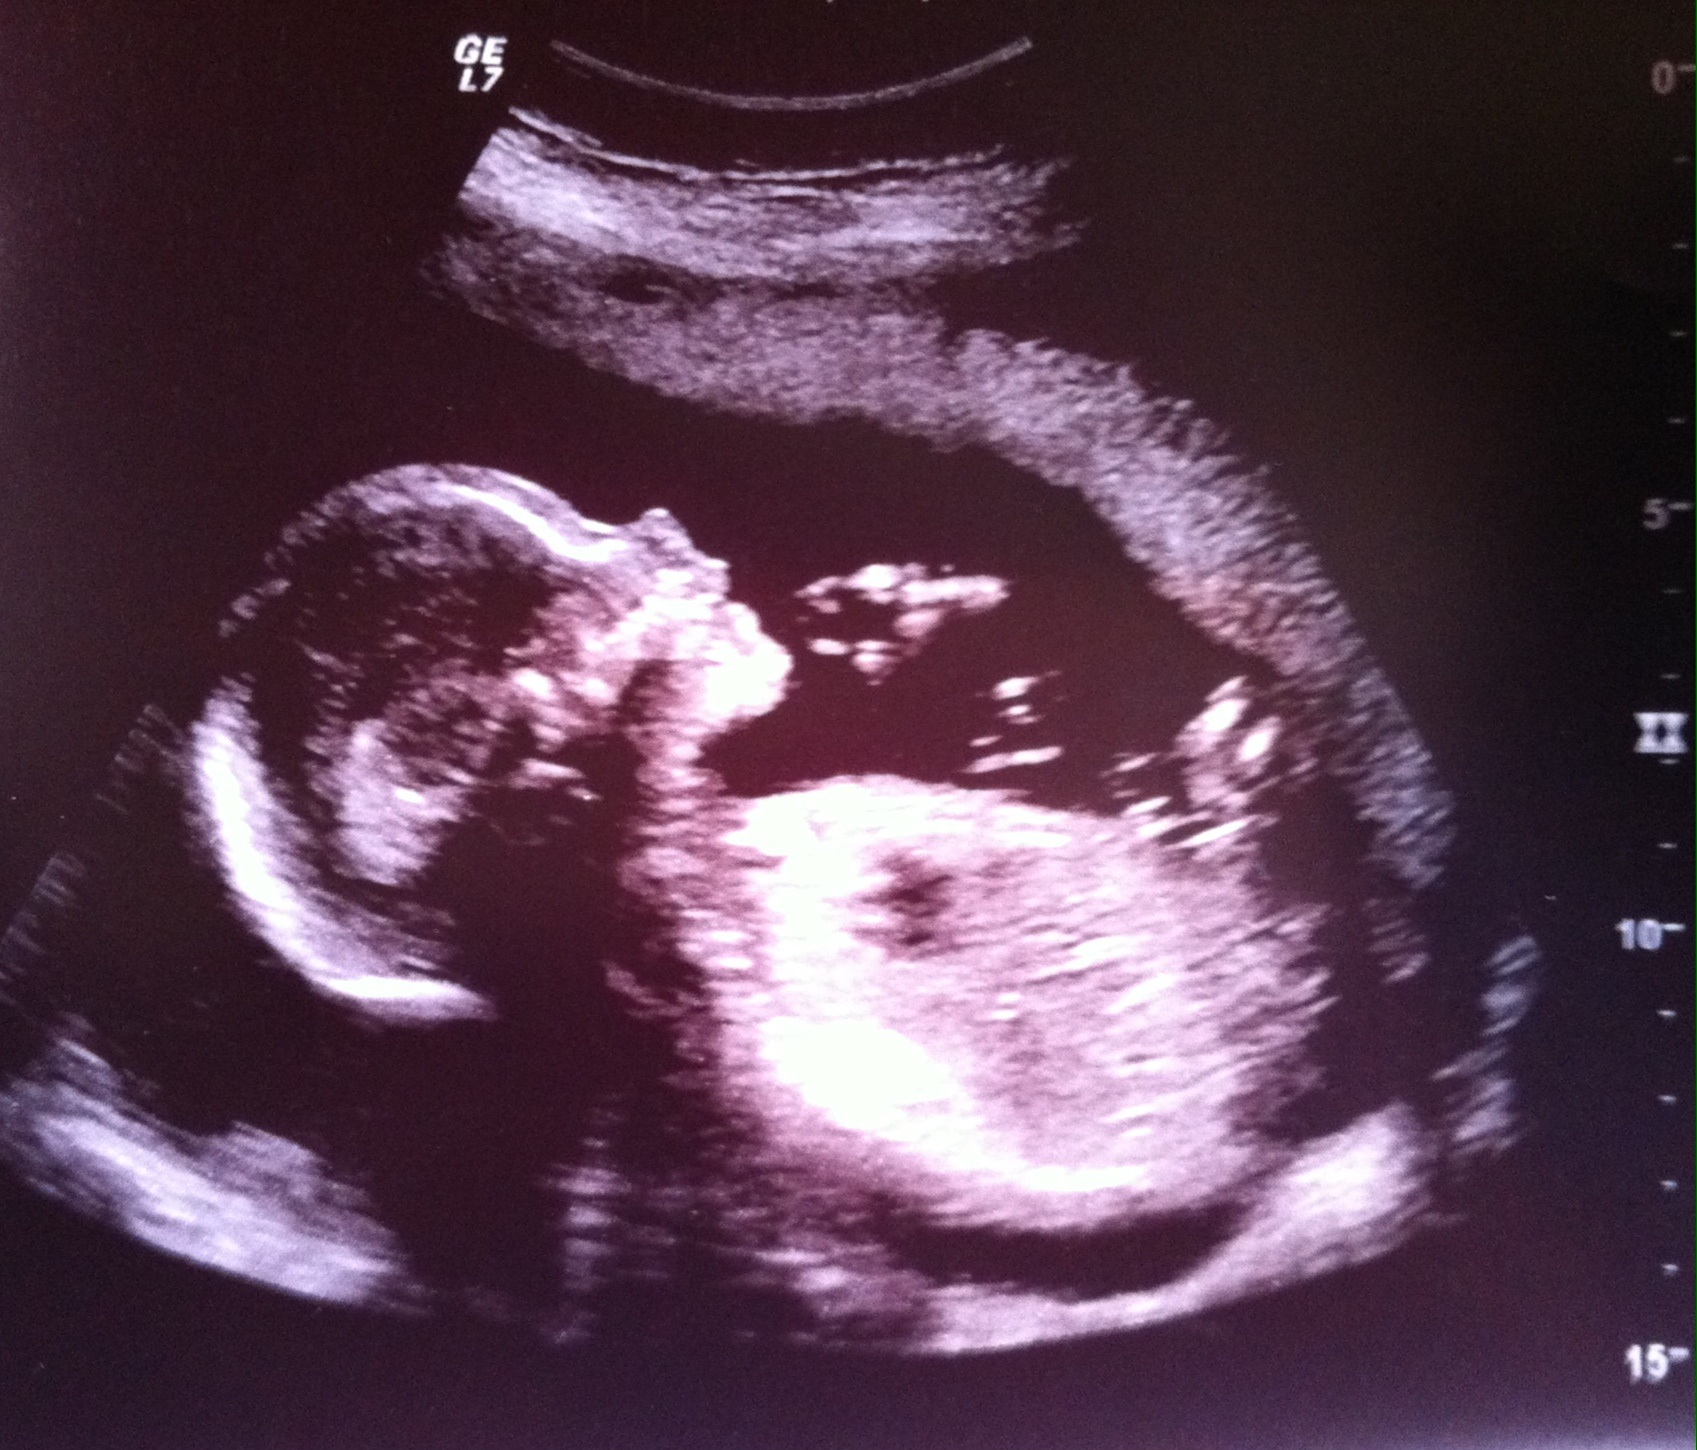

And then my latest u/s picture that I wasn't able to add to my AW post from my anatomy scan. Our little man William James